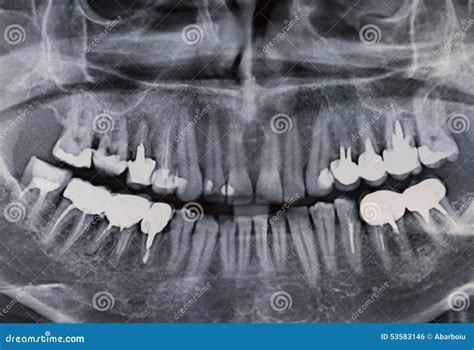

• Dental Implants: Crown X Ray Dental technology helps in planning the placement of dental implants by providing a detailed view of the jawbone and surrounding tissues.

• Orthodontic Treatment: Orthodontists use Crown X Ray Dental images to assess the position of the teeth and jaws, helping to plan and monitor orthodontic treatments.

• Oral Surgery: Surgeons rely on Crown X Ray Dental images to plan complex procedures, such as wisdom tooth extractions and jaw surgeries.